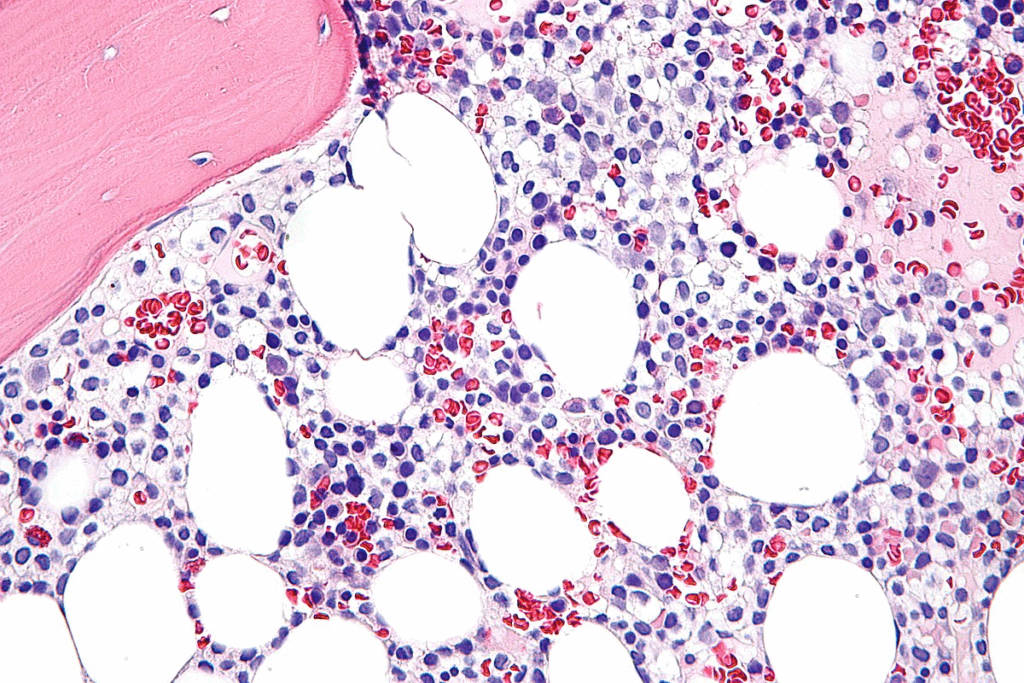

How Blood Cancer Affects Skin Appearance

Leukemia can change how the skin looks because it messes with blood cell production. It affects the bone marrow, leading to too many abnormal cells. This can cause skin changes like petechiae (tiny red or purple spots) and purpura (larger purple patches).

Low platelet counts can cause bruising and bleeding under the skin. This makes the skin change in visible ways. For example, petechiae appear in areas where the skin is pressed or hurt. These spots show small hemorrhages in the skin.

The Relationship Between Blood Cell Production and Skin Manifestations

Blood cell production is complex and happens in the bone marrow. Leukemia messes with this process, leading to too many bad white blood cells. These abnormal cells can get into the skin and cause different signs.